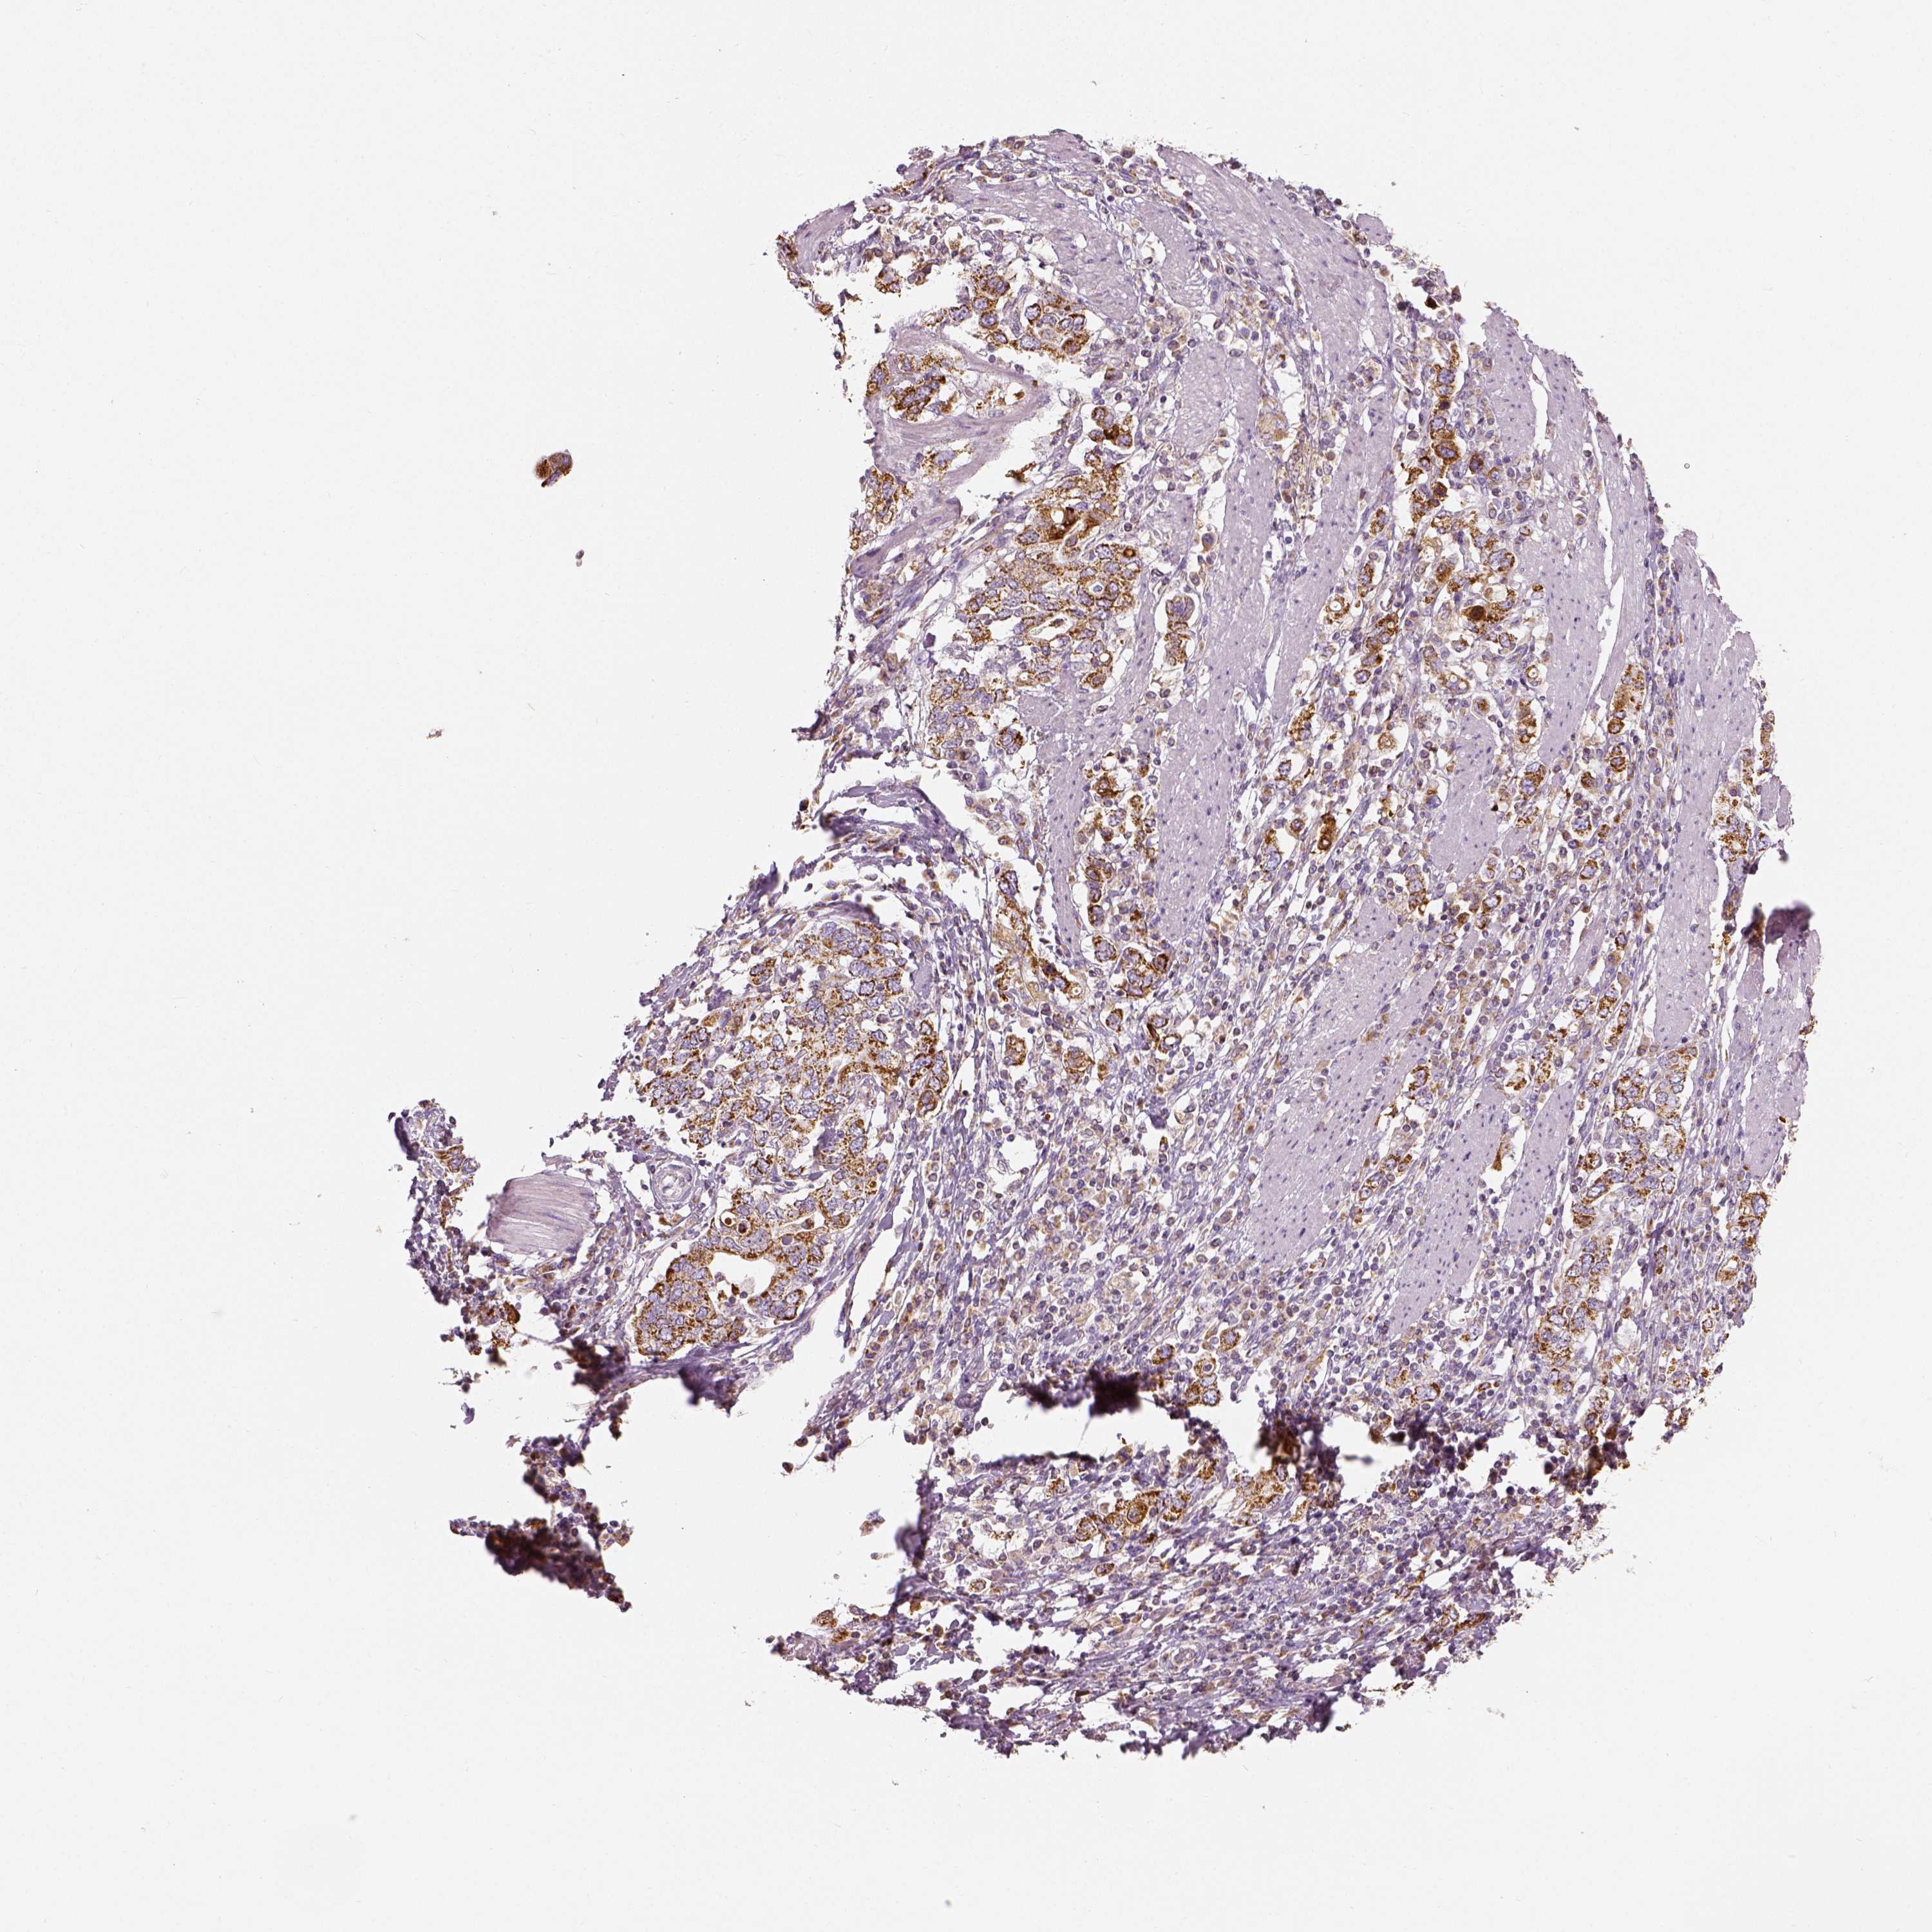

STOMACH CANCER - Protein expressioni

A mouse-over function shows sample information and annotation data. Click on an image to view it in a full screen mode. Samples can be filtered based on level of antibody staining by selecting one or several of the following categories: high, medium, low and not detected. The assay and annotation is described here.

Note that samples used for immunohistochemistry by the Human Protein Atlas do not correspond to samples in the TCGA dataset.

Antibody stainingi

Antibody staining in the annotated cell types in the current human tissue is reported as not detected, low, medium, or high, based on conventional immunohistochemistry profiling in selected tissues. This score is based on the combination of the staining intensity and fraction of stained cells.

Each image is clickable and will lead to virtual microscopy that enables deeper exploration of all samples and also displays staining intensity scores, fraction scores and subcellular localization as well as patient and tissue information for each sample.

Antibody HPA036978

Antibody HPA036979

Antibody CAB068215

Staining

High

Medium

Low

Not detected

Intensity

Strong

Moderate

Weak

Negative

Quantity

>75%

75%-25%

<25%

None

Location

Nuclear

Cytoplasmic/membranous

Cytoplasmic/membranous,nuclear

Adenocarcinoma, NOS